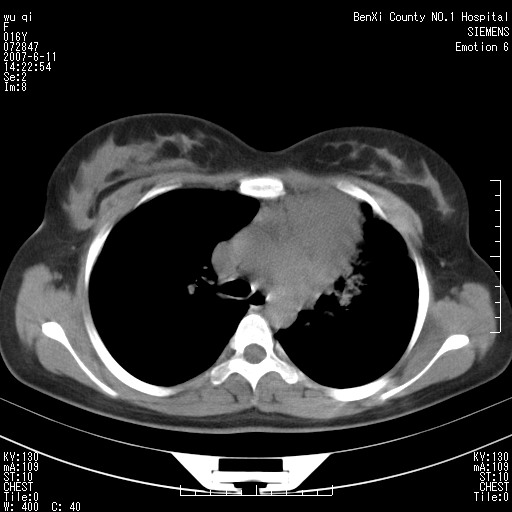

女.16、咳嗽、乏力、消受,食欲差,一个月余,无咯血,一个月前有发热。经抗炎治疗发热消失,仍咳嗽。平扫ct值34-45hu,增强后60-78hu明显强化,另外为了大家方便阅片,简单提下自己意见,纵隔内淋巴结肿大,左肺片影,其内密度不均,增强扫描明显强化,左肺上叶支气管可见支气管气象。尖段闭塞。冠状位可见左侧锁骨下静脉受压下移。请大家会诊,分析。

肺不张会引起纵隔结构向患侧移位,而该病例纵隔是向右侧移位,且左侧锁骨下静脉受压移位,均提示病灶位于纵隔内。我感觉象是淋巴瘤,左肺病灶是因为阻塞性肺炎引起的。

2、左上肺我认为是个不张的肺,仔细看左上肺体积有点缩小

看过病例,肿块位于左侧胸膜顶和上纵隔,呈巨大不规则形软组织密度,边缘不清楚,和上纵隔诸结构不好分界,并可见肿大淋巴结影,左上叶支气管尚通畅,但上叶肺组织可见压迫性不张和膨胀不良。肿块内部可见一条明显的粗大血管影,经多层面追踪,应该是左侧锁骨下静脉。从以上表现来看,肿块的起源应该是在肺外,大致来源于胸膜顶部,向下、内生长。增强扫描,肿块内部可见多发血管分支,证明肿块血供较为丰富,从这一点上,比较符合间叶组织来源的恶性肿瘤,淋巴瘤往往表现为多发肿大淋巴团,但增强扫描内部出现迂曲血管的几率比较低,我觉得不是太象。间叶组织类别非常多,该类肿瘤只靠影像学很难鉴别,经皮穿刺活检不失为最好的方法,可以首先考虑。

本病例个人考虑还是左上肺感染性病变伴左上肺固有上叶不张,左下肺代偿气肿.左下肺背段结节灶.结合临床首先为肺/纵隔淋巴结核.

定位定性理由:1 斜裂到哪里去了?明显的前上移位了.2 原"左上肺区域"透光度明显增高,肺纹稀疏,为肺气肿征象.3不是全上肺不张,而为固有上叶,可惜楼主的冠位图未明显显示.4 左下肺背段可见结节灶,紧贴脊柱旁,再仔细看看.5 胸膜改变显示支持是炎性病变.6那根血管我也仔细观察了,浓度同动脉,近端较粗,应为肺动脉,包括实变肺内的血管分支都应为肺动脉分支.7 实变内明显不均强化,更加支持炎性病变.8淋巴结肿大以弓旁为主,轻度均匀强化,中纵隔内未见明显淋巴结,面此区的淋巴肿最多见于结核;9实变近端无明显块影而不支持腔内肿瘤,虽然无典型的支气管狭窄直接征象.10 为什么纵隔向患侧移位不明显?因为肺容积缩小不是太显著,更多的是肺泡内较多渗出导致如此.11 实变外围的条片影从形态看不象纵隔肿瘤所致的压迫性肺炎,如为压迫应紧绕肿块环形分布.14 与纵隔结构有明显分界,而且从重组图像看病灶主体更象楔变而非肿块,有哪一种肿瘤可以导致下缘如此平直?

大家真的很厉害,痰查结核菌为肺结核,胸片可见抗结核治疗有效,胸片不是我们院拍的,所以,大家看不到了。^_^。